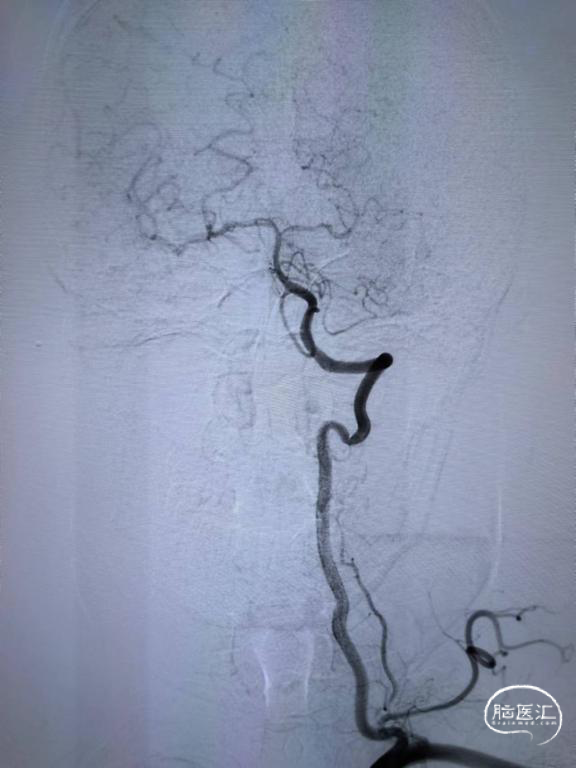

DSA示:右侧颈内动脉起始段闭塞,颈外动脉通过眼动脉代偿至眼动脉,前交通级后交通均开放,代偿右侧大脑中动脉供血。